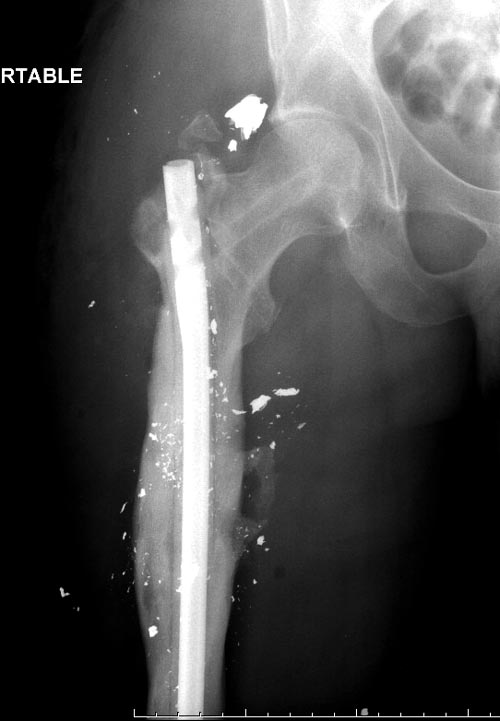

На снимках осложнение огнестрельного перелома бедра поздней инфекцией. 7 лет назад оперирован: правое бедро, сперва на ExFix, затем заменен на гвоздь, а левая - гвоздь при поступлении.

Беспокойство проявил недавно, по поводу жалоб на боли сделано МРТ и дренирование абсцесса терапевтами. Мы удалили гвоздь, сделали I&D, рассверливание канала, и ввели гвоздь с антибиотиком. Для гвоздя использовали стерильную трубку-форму, а антибиотик по 1.0 Tobramycin c Vancomycin.

В замкнутом без перелома пространстве во время риминга повышается давление внутри канала, и имеется риск тромбообразования. Для профилактики и для дренажа - каннюлированный винт 6.5 мм в дистальной части бедра. Обработку заканчивают культурой из раны и канала. Иногда процедуру надо будет повторить.

Гвозди с антибиотиком все custom made, т.е. делаются во время операции. Диаметр зависит от внутреннего диаметра канала. Обычно достаточным бывает 10 мм, и редко применяется готовые гвозди для армирования цемента. Трубка в 10 мм для плевральной полости как форма и армирование 2.8 или 3.2 мм guide wire для гвоздей, которая срезается по длине, на конце делается петля для облегчения удаления.

В представленном случае, из-за большого диаметра первичного гвоздя (13мм) применили готовый гвоздь в 11 мм, а трубка с внутренним диаметром 16 мм.